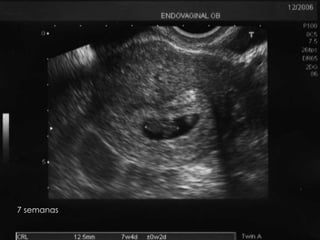

7 semanas